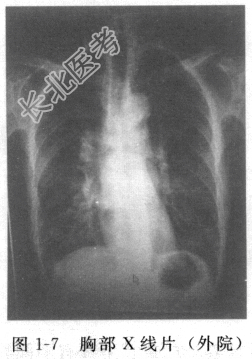

患者男性,32岁,因“反复发热伴咳嗽、咳痰1周”入院。入院前外院急诊血常规提示WBC 13.6×10

/L,N% 78%。胸部X线片(图1-7)示右下肺斑片状影。查体:双肺呼吸音粗,右下肺可闻及湿啰音。外院给予“头孢替安”等抗感染、退热等治疗后体温稍有下降,仍有反复咳嗽、咳痰。